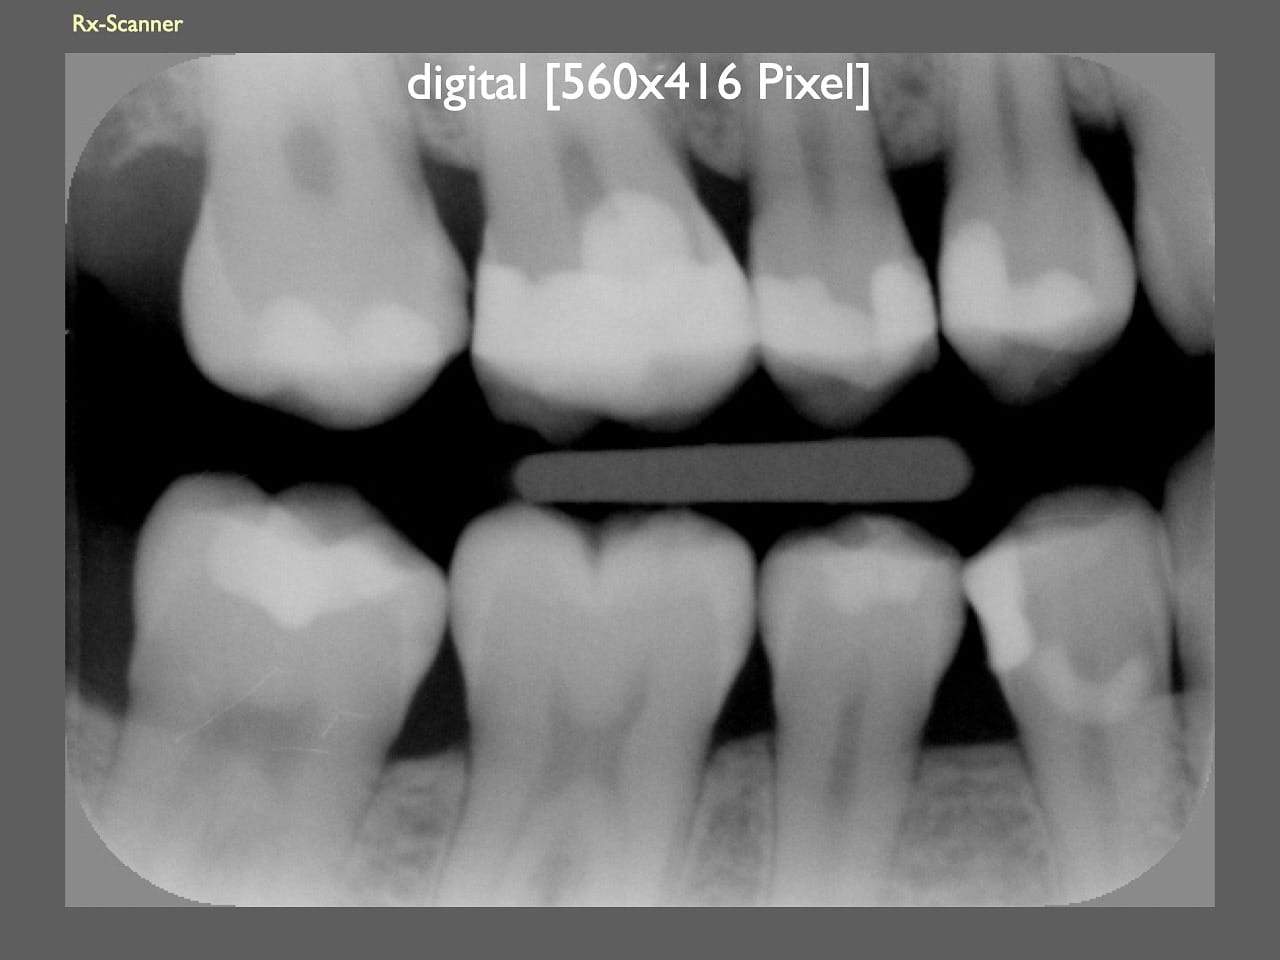

dental Scannen in der Zahnarztpraxis. Study Club vom 28.2.2010. Von peter portmann, Veröffentlicht am 28. Feb. 2010 — 3 min Lesezeit dokumentationfoto Auf dieser Seite Zahnarztpraxis-Trilogie zu Fotografie und Dokumentation Portrait Fotografie Scannen Scannen